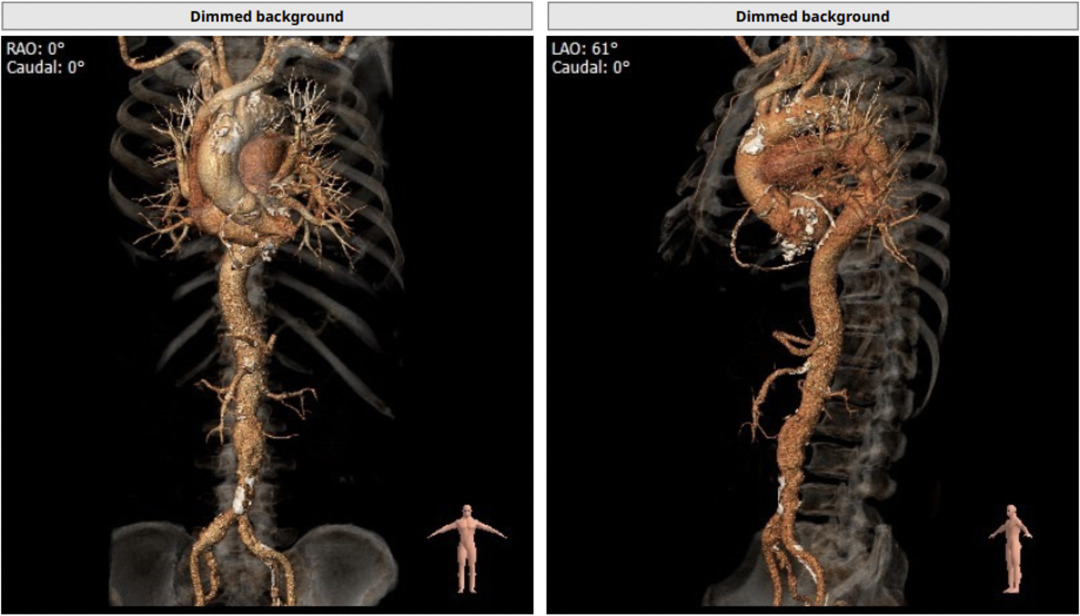

瓣环平均直径:20.1 mm,左室流出道平均直径:20.8 mm

左冠开口高度:10.6 mm,存在冠脉风险;心脏呈横位,角度约为60°

钙化积分:419.9 mm³,中度钙化

左室大小尚可,心尖部位薄弱

CT评估结果显示,患者为三叶瓣,中度钙化,法式窦结构相对可,右冠高度可,左冠开口高度低,瓣叶上缘达左冠开口下缘,植入主动脉瓣膜后有一定概率压迫冠脉开口,冠脉阻塞风险较高。横位心,心脏角度约60°,左室大小可,升主动脉未见明显扩张。术前CT提示患者术后房室传导阻滞发生概率较高,手术操作复杂风险较大。